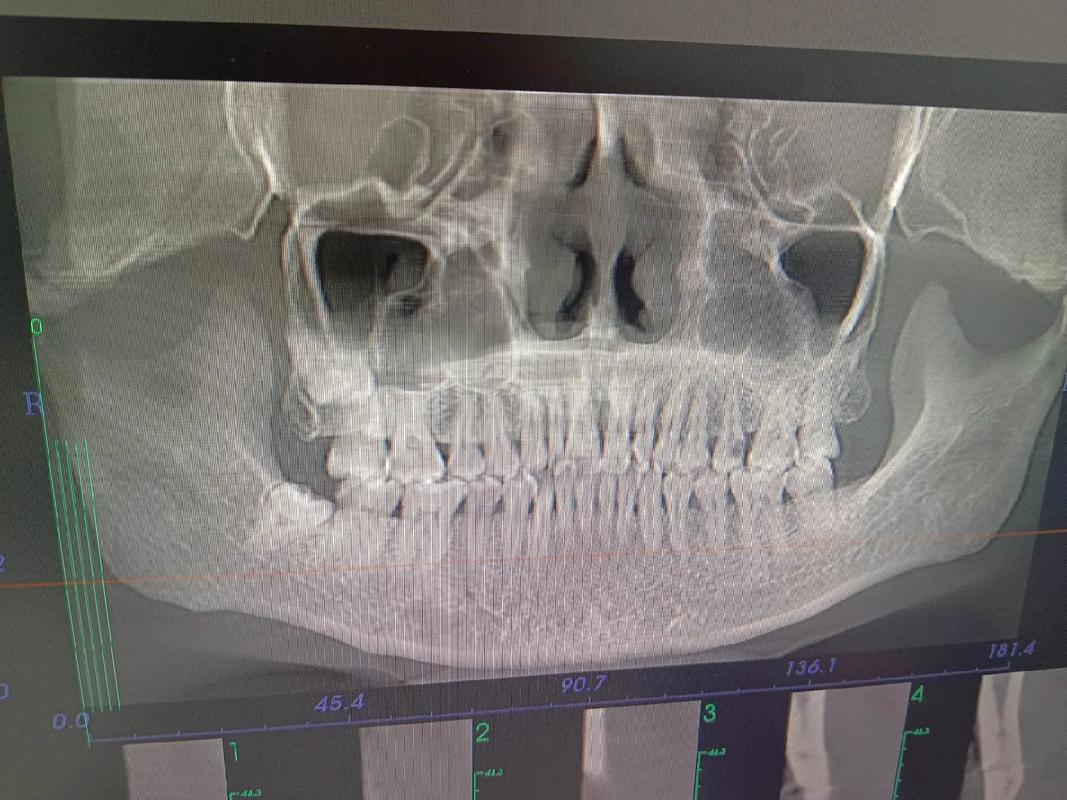

- 对于一些复杂的、涉及骨骼、埋伏牙、种植支抗或需要精确评估骨量的情况,口腔CT(CBCT)是极其重要甚至不可或缺的诊断工具。

三维可视化:

- 埋伏牙定位: 对于未萌出的牙齿(如埋伏阻生智齿、尖牙、多生牙),CBCT能清晰显示牙齿在颌骨内的精确位置、萌出方向、牙根形态以及与邻牙、重要解剖结构(如下颌神经管)的关系,这是二维片无法比拟的,对制定手术导萌或正畸牵引方案至关重要。

- 牙根位置与吸收: 可以清晰观察牙根在牙槽骨内的位置、有无弯曲、以及是否有牙根吸收(尤其是正畸治疗过程中或治疗后需要评估时)。

- 牙槽骨量评估: 在需要植入种植体作为支抗(如种植支抗钉)或评估拔牙后牙槽骨情况时,CBCT能精确测量牙槽骨的厚度、高度、密度,判断是否足够容纳种植体或支持牙齿移动。

- 颌骨形态与不对称: 对于严重的颌骨发育问题(如下颌偏斜、面部不对称),CBCT能提供颌骨三维形态的详细信息,帮助制定复杂的正畸正颌联合治疗方案。

- 颞下颌关节(TMJ)评估: 当怀疑有关节盘移位、骨关节病等问题时,CBCT能清晰显示关节骨性结构的变化。

- 牙根移动模拟: 在数字化正畸中,CBCT数据可以与口内扫描数据结合,建立精确的三维牙颌模型,进行虚拟牙齿移动模拟,预测治疗结果,制定更精准的方案。

- 气道评估: 对于有睡眠呼吸暂停倾向或需要评估气道空间的患者(尤其涉及下颌后缩或上颌垂直向发育问题),CBCT可以测量咽腔容积和横截面积,辅助诊断和治疗决策。

- 正畸手术规划: 对于需要正颌手术的患者,CBCT是手术模拟和制定手术方案的基础。

- 复杂正畸: 当涉及埋伏牙、种植支抗、骨骼问题、精确骨量评估、疑难杂症等情况时,口腔CT(CBCT)是非常必要的诊断工具,能提供二维影像无法企及的关键信息,有助于制定更精准、更安全、更可预测的治疗方案,并降低治疗风险。